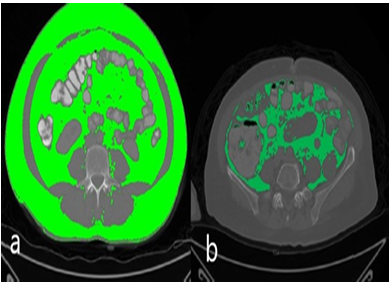

Imaging was performed using a 128-detector multidetector computed tomography system (Philips Ingenuity 128, Eindhoven, The Netherlands). For all phases, the following technical parameters were utilized: tube voltage, 120 kVp; automatic tube current modulation, 200–400 mAs; rotation time, 0.42 s; pitch, 0.6; and slice thickness, 1 mm. Contrast- enhanced scanning was performed through the injections of saline, non-ionic iodinated contrast media, and finally 20 ml of saline, in sequential order, all via the antecubital vein, administered using an automatic infusion pump. Oral contrast was also administered. All measurements were performed in the portal venous phase, and the CT images were reviewed in a soft-tissue window at a workstation (Intelli SpacePhilips [IPS], The Netherlands). Abdominal and mesorectal adipose tissue volumes were calculated using − 130 to − 30 Hounsfield unit (HU) values for adipose tissue voxels (Fig. 2). The abdominal adipose tissue compartment was defined as the space between the diaphragmatic esophageal hiatus and the symphysis pubis, and visceral fatty tissue was composed of the mesenteric, subperitoneal, and retroperitoneal fatty compartments. According to the study protocol, total adipose tissue volume was calculated first, followed by visceral and subcutaneous fat tissue volumes. Two radiologists reviewed all images for accuracy, making manual corrections when necessary to exclude solid organs, intestines, blood vessels, and fat-free tissues (such as bone) from the measurement areas. The visceral, subcutaneous, and mesorectal fat tissue volumes were measured in millimeters and automatically processed by the software. All measurements were performed by two radiologists based on consensus. For the measurements, all images obtained from the software were used. No extrapolation procedures such as addition and multiplication were utilized to ensure the calculation of the real adipose tissue volumes.

Figure 1. Axial computed tomography measurements: a) total fat volume b) visceral fat tissue volume